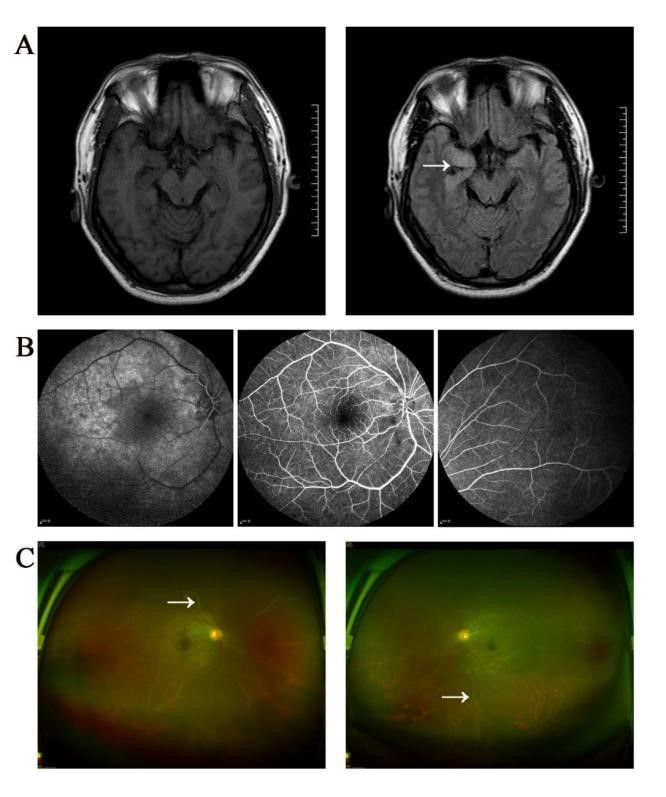

Minh họa: (A): Chụp cộng hưởng từ T2-FLAIR cho thấy tín hiệu hơi cao ở phần trước và phần giữa của thùy thái dương (được biểu thị bằng mũi tên); (B): Chụp động mạch đáy mắt cho thấy động mạch được làm đầy chậm, tắc mạch một phần và lưu lượng máu thay đổi như hạt; (C): Nội soi đáy mắt cho thấy thủy tinh thể mờ đục, tắc mạch máu một phần ở ngoại vi võng mạc và các đặc điểm "giống như đường trắng" (được biểu thị bằng mũi tên)